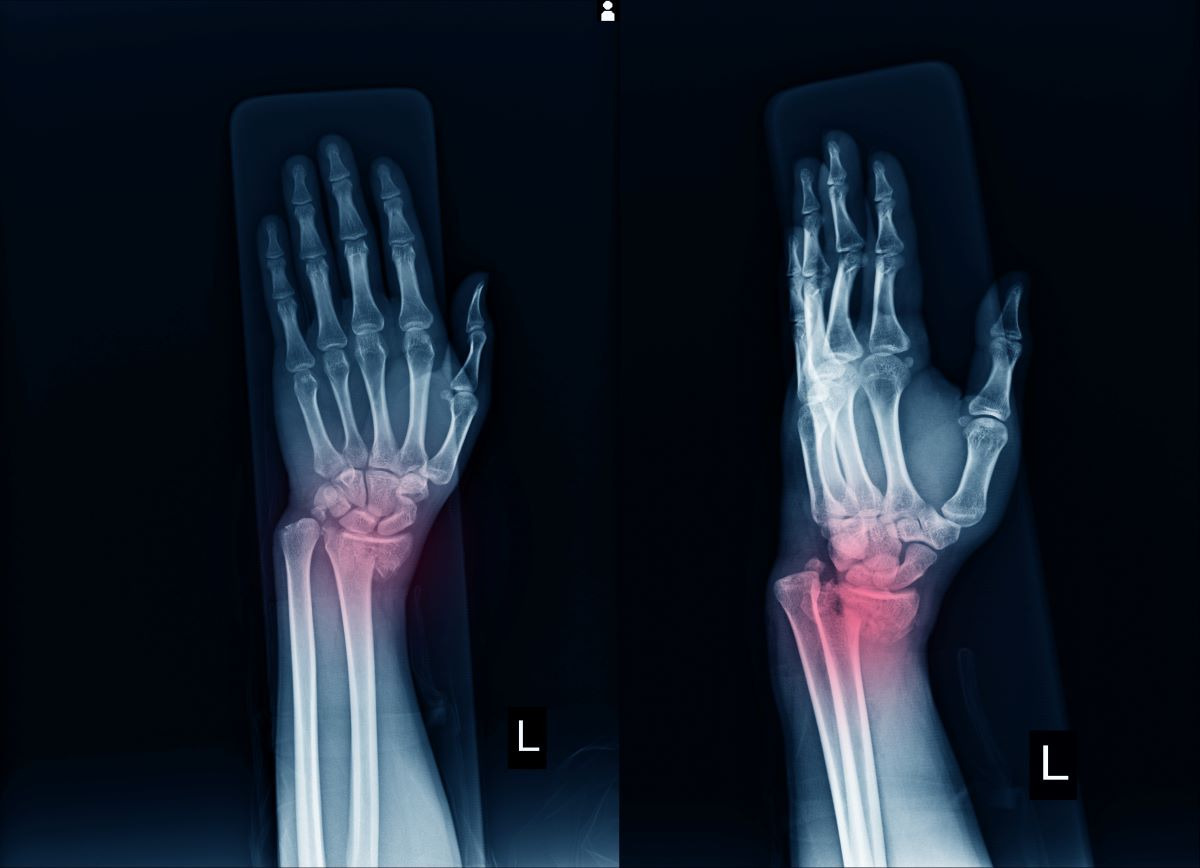

손목 골절은 손목 관절을 이루는 요골·척골 중 특히 요골 원위부 골절이 가장 흔하게 발생합니다. 넘어지면서 손을 짚거나, 교통사고·스포츠 손상 등 외부 충격으로 뼈가 부러질 수 있습니다. 골절은 단순히 뼈만 부러지는 것이 아니라 주변 인대·근육·신경까지 손상될 수 있어 치료와 회복에 긴 시간이 필요합니다.

- 치료 방법: X-ray 확인 후 뼈를 맞추는 정복(整復) → 깁스로 고정

- 적용 대상: 복합 골절, 분쇄 골절, 관절면 침범 골절

- 치료 방법: 금속 핀·플레이트·나사로 뼈를 고정